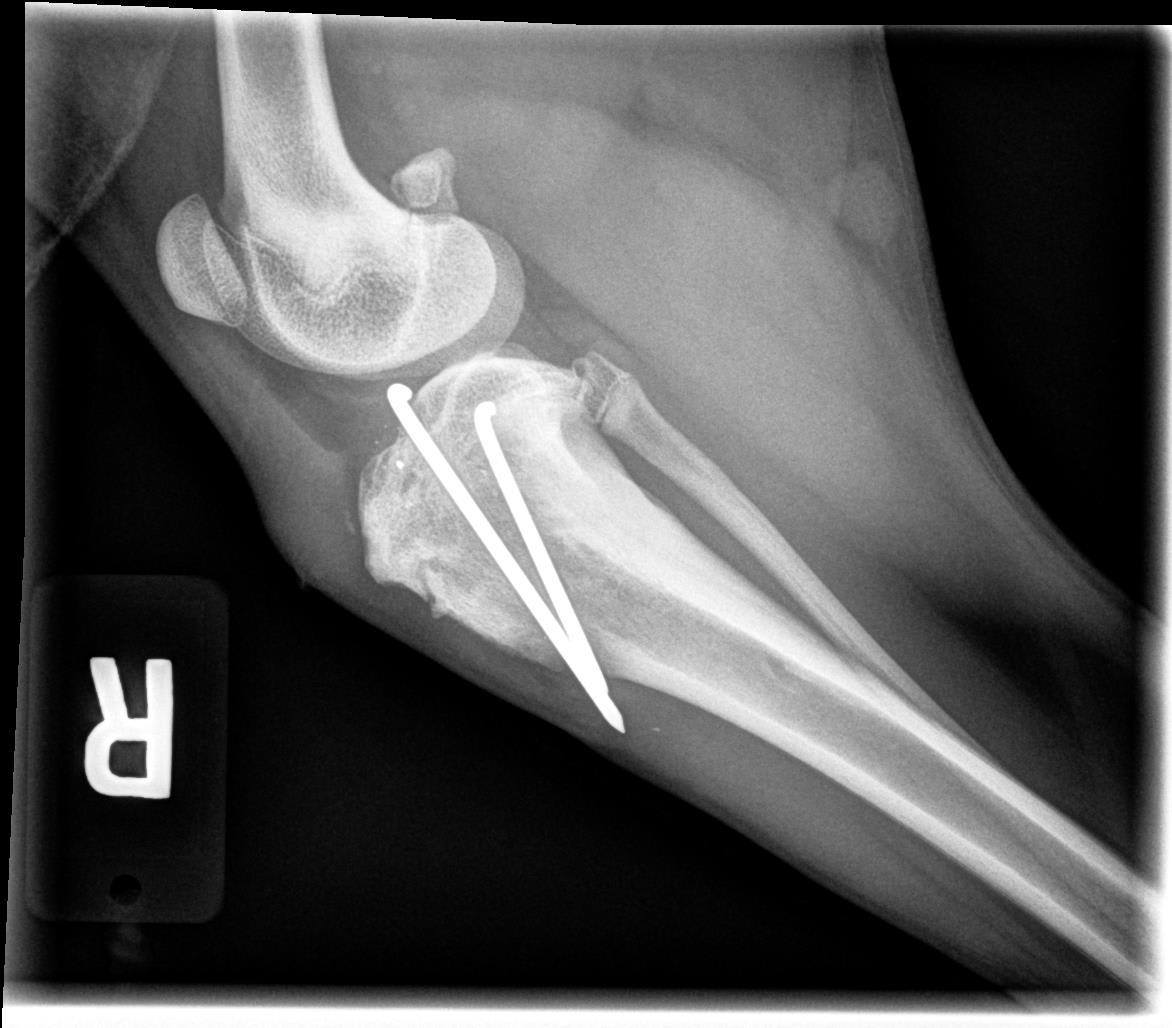

My puppy had surgery on his leg 7 weeks ago after a tibial fracture. They sent me the xrays of the healed bone and it looks like the pins are sticking all the way through the bone and coming out on the other side. The doctor said he is fine and the pins can remain in place for the rest of his life. They look sharp and I can feel a bump where they are through his skin. It looks very strange. Is this normal? The image with three pins is from 2 weeks ago before one of the pins had to be removed.

Hello and thank you for reaching out to Petco Pet Education Center, formerly Petcoach! It is normal for pins to be placed so that they stick out the other cortex (side) of the bone, as this ensures they have a good hold on the fracture fragments to prevent any movement of the fragments. As long as Toby does not develop an infection in his bone around any of the pins, and he is not exhibiting any discomfort from them, he will likely be able to have the pins in for the rest of his life. If you notice that the pins seem to be protruding more than usual, or if Toby is lame/painful on the affected leg, it is possible the pin(s) could have migrated inappropriately and/or could have become infected. This would require a visit to your veterinarian for an exam and repeat x-rays, and potentially surgery to remove the pins. I hope this helps :)